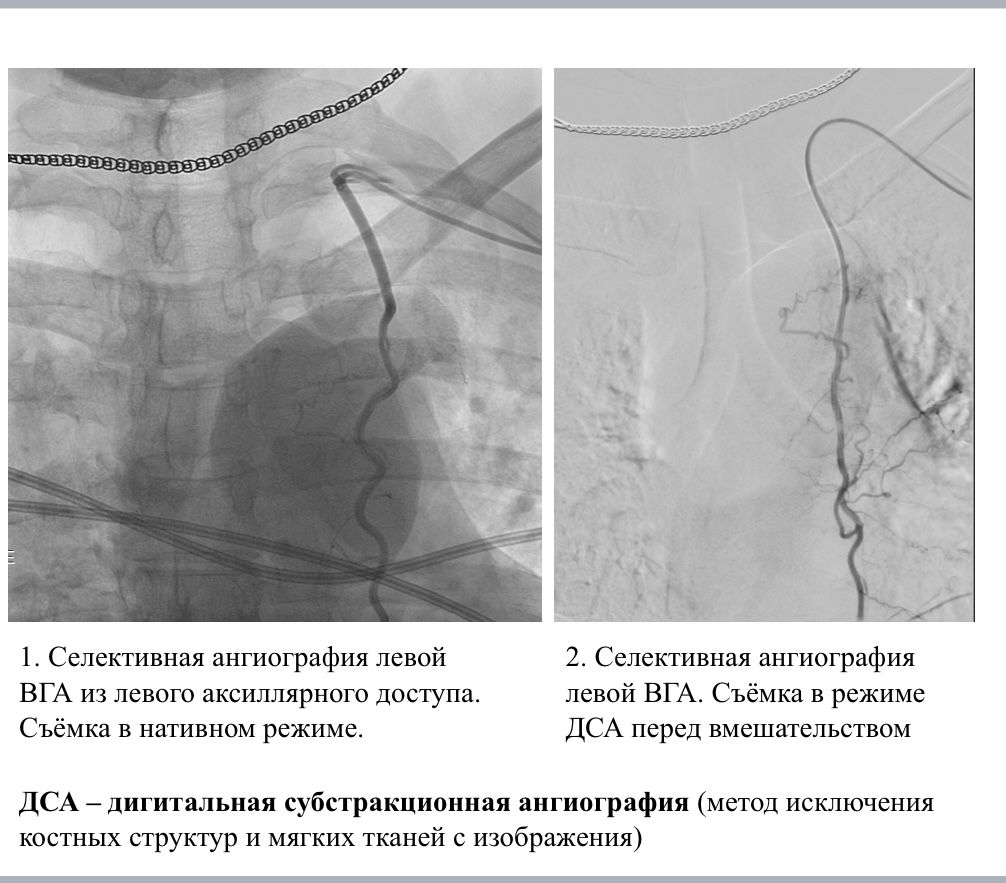

Суть инновационного подхода — в доставке химиопрепарата напрямую к опухоли через питающие ее артерии. Как пояснили в минздраве области, это дает целый ряд решающих преимуществ:

Именно это и произошло с воронежской пациенткой. Курс селективной химиоинфузии позволил снизить массу и объем опухоли до состояния, когда стало возможным хирургическое вмешательство. Врачи успешно выполнили мастэктомию, после чего женщина ушла в ремиссию. Медикам удалось остановить распространение рака в другие органы.